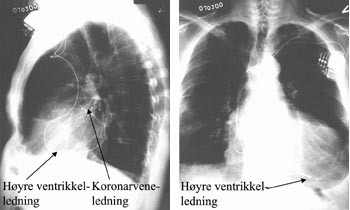

Pasient 5 er en 71 år gammel mann som hadde hjerteinfarkt for 16 år siden, aortokoronar bypassoperasjon for 13 år siden, paroksystisk atrieflimmer og høyresidig parietalt hjerneinfarkt med lett dysartri som sekvele for 12 år siden (tab 1). Han fikk permanent ventrikkelpacemaker pga. takybradyarytmi for sju år siden. Tross opptrapping av den medikamentelle behandlingen, har han hatt gradvis forverring av hjertesvikt til funksjonklasse IV (tab 1, 2). Det ble implantert biventrikulær pacemaker etter den angitte metoden med koronarveneledning plassert i en lateral vene (tab 3). Da man skulle fjerne den lange hylsen til sinus coronarius, drog denne med seg pacemakerledningen idet den kom ut av sinus coronarius-munningen. Det lot seg ikke gjøre å plassere ledningen tilbake til den opprinnelige gode posisjonen som gav lav stimuleringsterskel. Pasienten var sliten og man måtte derfor avslutte operasjonen.

Da en ny pacemakerledning (Medtronic ”AttainTM Side-Wire” 4191) var tilgjengelig, valgte vi å fjerne den gamle ledningen og implantere den nye. Ved denne prosedyren ble angioplastikk-ledesonde benyttet (Schimed Choice TM, Boston Scientific). Pacemakerledningen ble ført til koronarvenen over denne ledesonden via en meget liten sidering (tab 3). Pasienten har fått betydelig bedret kardial funksjonskapasitet og mer enn fordobling av ejeksjonsfraksjonen (tab 5).